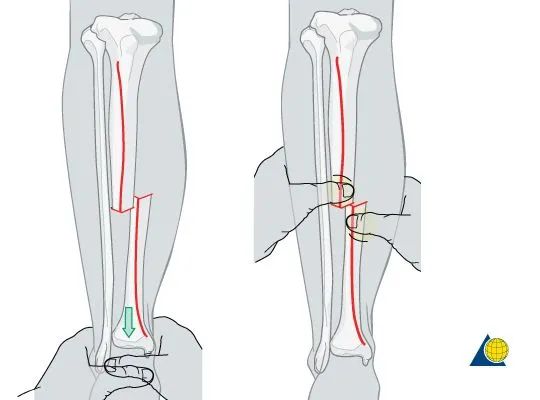

进行纵向的牵引来恢复长度是首要的,

然后同时可以纠正力线和旋转。

手指触摸胫骨前方的骨折断端来进行骨折的复位,

横行的骨折可以通过复位后较好的呆在复位后的位置,

但斜行的比较困难。

横行的复位差不多了后,进行力线和旋转的复位,

以骨折断端胫骨前内侧为模板进行复位,

然后观察整体的力线和旋转。